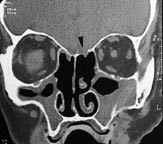

Pasienten gjennomgikk så evulsio samt endonasal etmoidektomi og antrostomi bilateralt i narkose. Det ble peroperativt bemerket noe aderent concha media på høyre side og noe uoversiktlige forhold, muligens etter tidligere operasjon. Det oppstod en arteriell blødning fortil i etmoidaltaket, som stanset etter komprimering over noen minutter med en adrenalintampong. Ingen øvrige komplikasjoner ble observert i det videre forløp, og pasientens umiddelbare postoperative tilstand var upåfallende. Neste dag utviklet han så en global hodepine som ble forverret ved forsøk på oppreist stilling. 3. postoperative døgn klaget han over rennende nese når han bøyde seg fremover. Han var preget av meningeal irritasjon, men man fant ingen reell nakkestivhet. Penicillin intravenøst ble administrert og man tok prøver av væsken til beta-2-transferrin-undersøkelse. Ny cerebral CT viste betydelige mengder luft i subaraknoidalrommet samt en ca. 5 mm stor defekt i skallebasis, lokalisert til etmoidaltaket på venstre side (fig 2). Ved ny skopi med 0˚ optikk fant man ingen pågående lekkasje. Blodprøvene viste maksimal CRP-stigning til 47, leukocytter 11,3, normale elektrolytter og kreatinin. Beta-2-transferrin-elektroforesen var positiv, hvilket indikerte lekkasje av spinalvæske. Pasienten ble observert kontinuerlig, og ny CT, som ble tatt 13 dager postoperativt, viste tydelig regresjon av den intrakraniale luften. Pasienten ble utskrevet i velbefinnende samme dag.

Ved avtalt kontroll ved poliklinikken sju uker etter operasjonen fant man ved CT ingen tegn til pneumocephalus. Pasienten hadde nå ingen nasalstenose eller rhinoré (fig 3).